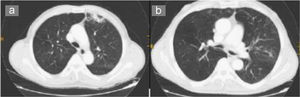

Al año el paciente fue remitido de nuevo por empeoramiento de la disnea hasta ser de reposo, acompañada de expectoración hemoptoica en 5 ocasiones durante el mes previo al ingreso y fiebre de 38°C. Las pruebas complementarias realizadas durante este ingreso fueron una analítica general, donde destacaban la cifra de leucocitos (15.600/dl), velocidad de sedimentación globular de 24mm/h, proteína C reactiva de 3,8mg/dl y presión arterial de oxígeno de 52,6mmHg. Se realizó una radiografía de tórax que mostró una condensación en el lóbulo inferior derecho. Los valores de la espirometría fueron los siguientes: volumen espiratorio forzado en el primer segundo del 32% y capacidad vital forzada del 45%. Se completó el estudio con una TAC torácica donde destacaban imágenes seudonodulares en el segmento anterior del lóbulo superior izquierdo y campo pulmonar medio derecho, así como agrupamiento de estructuras broncovasculares con atelectasias laminares y múltiples tractos fibrosos en ambas bases pulmonares (fig. 1a).

En consultas se recibió la identificación del germen como D. pneumosintes, por lo que se decidió prescribir amoxicilina-ácido clavulánico en ciclos de 10 días de tratamiento al inicio del mes, además de recomendar tratamiento a cargo de odontología. Tras 4 meses de seguimiento desaparecieron las lesiones en la TAC (fig. 1b). El paciente no ha presentado nuevos episodios.